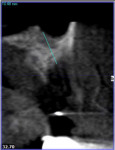

The area was irrigated with 0.12% chlorhexidine gluconate, and a cone-beam computed tomography (CBCT) was exposed to determine if implant placement using an allograft ring was an option. The scan revealed that an implant could be placed in a restoratively driven fashion utilizing the apical native bone, which would stabilize the fixture and allograft ring (Figure 4). Sinus involvement was ill-advised due to the patient's smoking addiction. It was decided to use a Narrow Connection Straumann® Bone Level Tapered Implant in position No. 12 and a Regular Connection Straumann® Bone Level Tapered Implant in position No. 13, necessitating the use of a 7-mm diameter Straumann® AlloGraft Ring. Standard surgical protocol was followed in the preparation of the osteotomy for the allograft ring and implant. This included identifying the appropriate site, marking it with round burs, and drilling to depth with a 2.2-mm diameter twist drill. A 7-mm trephine with copious irrigation was used to create the osteotomy, and a planator was used to flatten the floor.